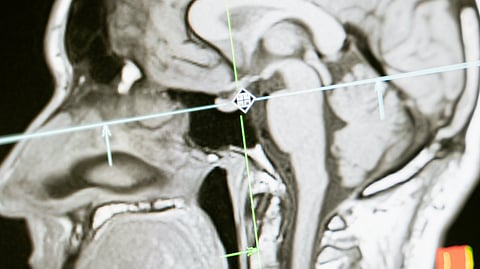

MRI scan of a human head in profile.

An MRI image of a human brain.MART PRODUCTION/ Pexels